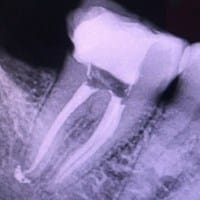

¿Con la extracción de muela con endodoncia sobreobturada, también saldrá el cemento intruso y se solucionara el problema

Estimada Alejandra, no te preocupes ya que al momento de la extracción la sobre obturación saldrá con todo el diente y sino con una cureta de alveolo tu dentista terminará de retirarlo; por otro lado gracias por enviar la foto de tu radiografía, allí...